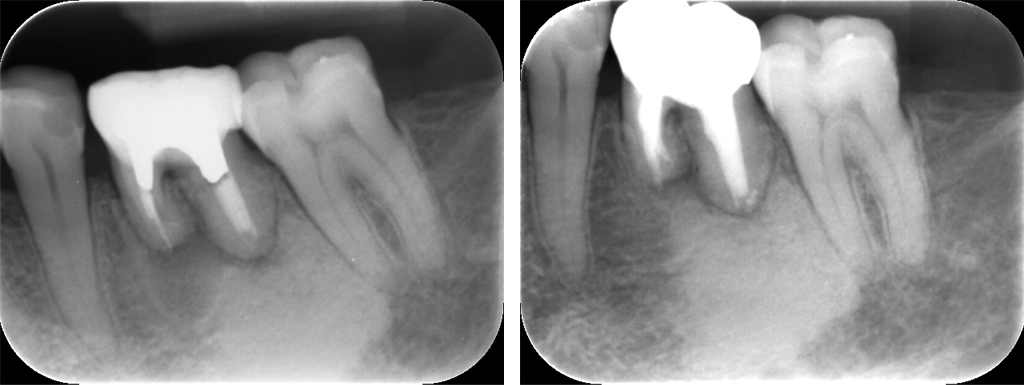

症例9:精密根管治療による治療3